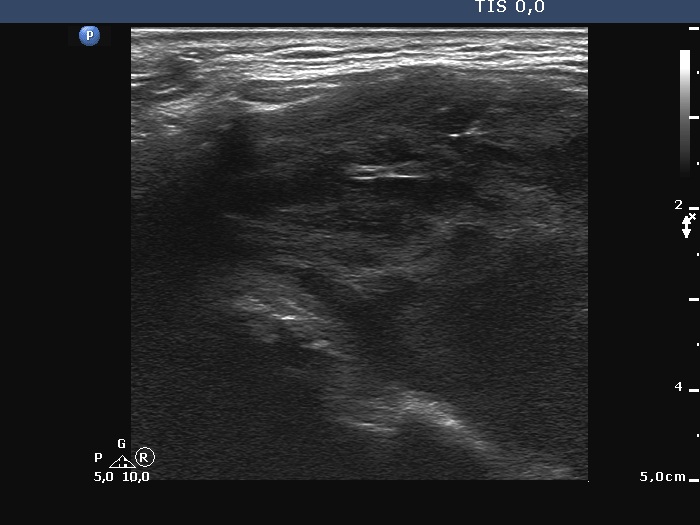

Thyroid cancers - case 1167 (ultrasonographic picture 3)

Right lobe, longitudinal scan. This is a very edifying pattern regarding the shorter and longer hyperechoic lines. The mechanism responsible for the presence of these lines is probably similar (or identical) to that of back wall cystic figures: dorsal to tissue with decreased echogenicity, the ultrasound wave amplifies.